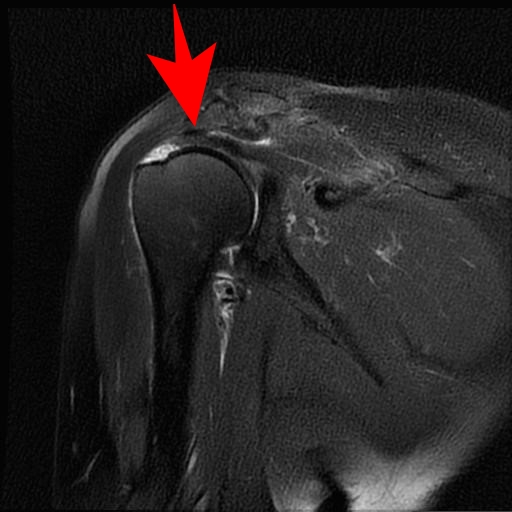

肩腱板断裂

40歳以上の男性に好発します(男女比6:4)。発症ピークは60代であり、来院理由の多くは寝ていられないほどの痛み(夜間痛)が動機になります。

原因・病態

肩関節腱板は4つの筋肉(棘上筋・棘下筋・小円筋・肩甲下筋)で構成されており、ローテーターカフと言われています。これば上腕骨と肩甲骨をつなぐ板状の腱で、腕を上げたり下げたりする時に上腕骨頭が肩甲骨の関節窩とずれないように保つ働きがあります。

これが損傷・断裂すると腕の上げ下げで肩関節の支点がとれなくなり、痛みや引っかかりなどの症状が出ます。

加齢による腱板の変性を基盤として、転倒など様々な程度の外傷が加わって断裂することが考えられています。腱板は肩峰と上腕骨頭の間に挟まれる形をしており反復的な挟み込みストレスを受けやすいことも一因です。

※炎症しているところが白く映っています。